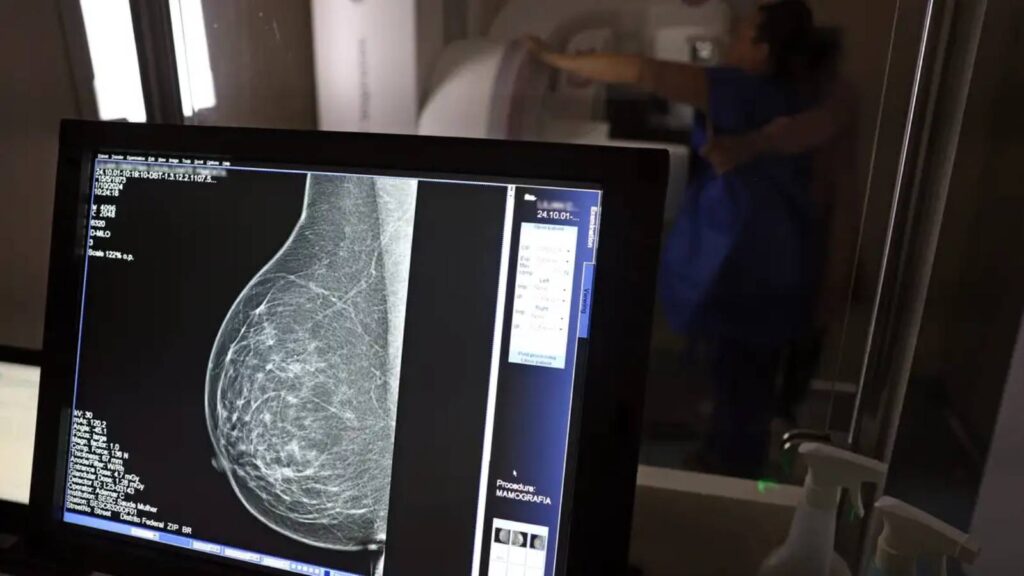

Assinada pelo presidente Luiz Inácio Lula da Silva e pelos ministros Alexandre Padilha (Saúde), Macaé Evaristo (Direitos Humanos e da Cidadania) e Márcia Lopes (Mulheres), a nova lei altera a Lei nº 11.664, de 29 de abril de 2008, que dispõe sobre a efetivação de ações de saúde que assegurem a prevenção, a detecção, o tratamento e o seguimento dos cânceres do colo uterino, de mama e colorretal no âmbito SUS. Agora, o texto determina que o exame de mamografia será garantido a todas as mulheres a partir dos 40 anos, conforme diretrizes do Ministério da Saúde, que poderão estender o procedimento a outras faixas etárias.

A garantia ao exame se dará mesmo que as mulheres não apresentem sinais ou sintomas de câncer. A faixa etária dos 40 aos 49 anos concentra 23% dos casos da doença e a detecção precoce aumenta as chances de cura.

A recomendação para as mulheres a partir dos 40 anos é que o exame de mamografia seja feito sob demanda, em decisão com o profissional de saúde. A paciente deve ser orientada sobre os benefícios e desvantagens de fazer o rastreamento. Mulheres nesta idade tinham dificuldade com o exame na rede pública de saúde em função da avaliação de histórico familiar ou necessidade de já apresentar sintomas. Apesar disso, as mamografias no SUS em pacientes com menos de 50 anos representam 30% do total, equivalente a mais de 1 milhão em 2024.

AMPLA COBERTURA — Em 2024, o Sistema Único de Saúde (SUS) realizou aproximadamente 4 milhões de mamografias para rastreamento e 376,7 mil exames diagnósticos. Esses números refletem a manutenção de uma ampla cobertura no país, reforçando a importância do rastreamento e do diagnóstico precoce para salvar vidas e garantir mais qualidade na atenção à saúde das mulheres.